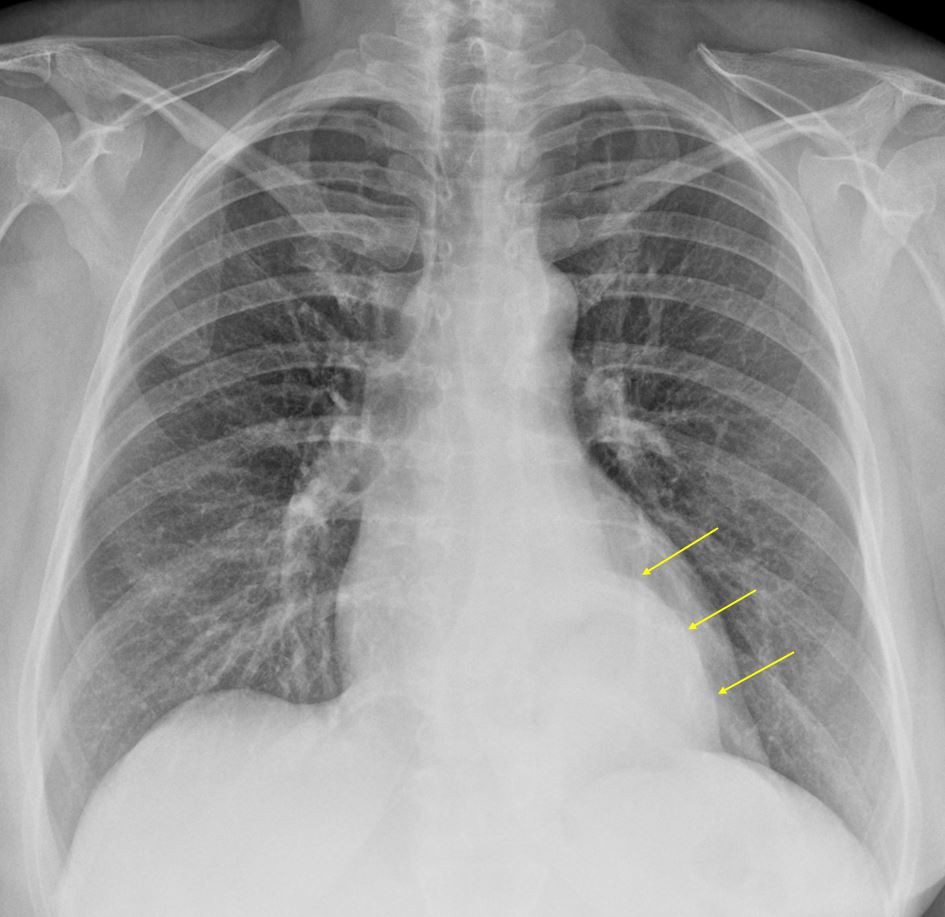

Paraesophageal hernia x ray

Paraesophageal Hernia X Ray www.animalia-life.club

Chest X Ray Hiatal Hernia At Tamie Rowe Blog

Chest X Ray Hiatal Hernia at Tamie Rowe blog dxogbtlhh.blob.core.windows.net

hernia hiatal hiatus ray lateral thorax stomach chest radiograph im diagnosis des license sa cc arrow liquid air treatment mirror